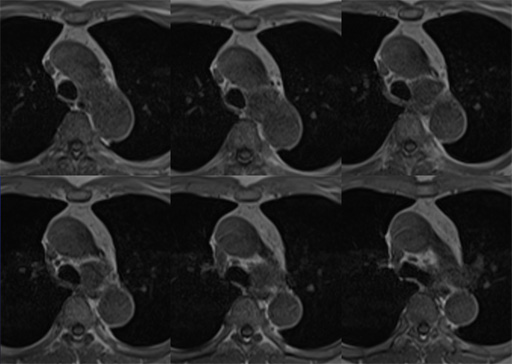

症例7 : 図7 MRI T1WI (in phase)

症例7 : 図8 MRI T1WI (out of phase)